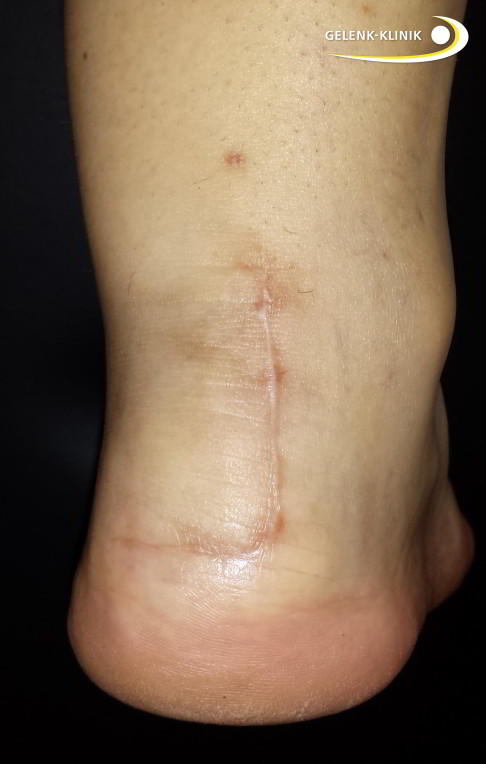

- Viel kleinere Narben, die sich nicht über die gesamte Länge der Ferse ziehen und in festen Schuhe zu Irritationen, Druckgefühl und Fersenschmerzen führen

- deutlich geringere Weichteilverletzung

- schnellere Heilung und Regeneration, Fadenzug i. d. R. bereits nach 7 Tagen